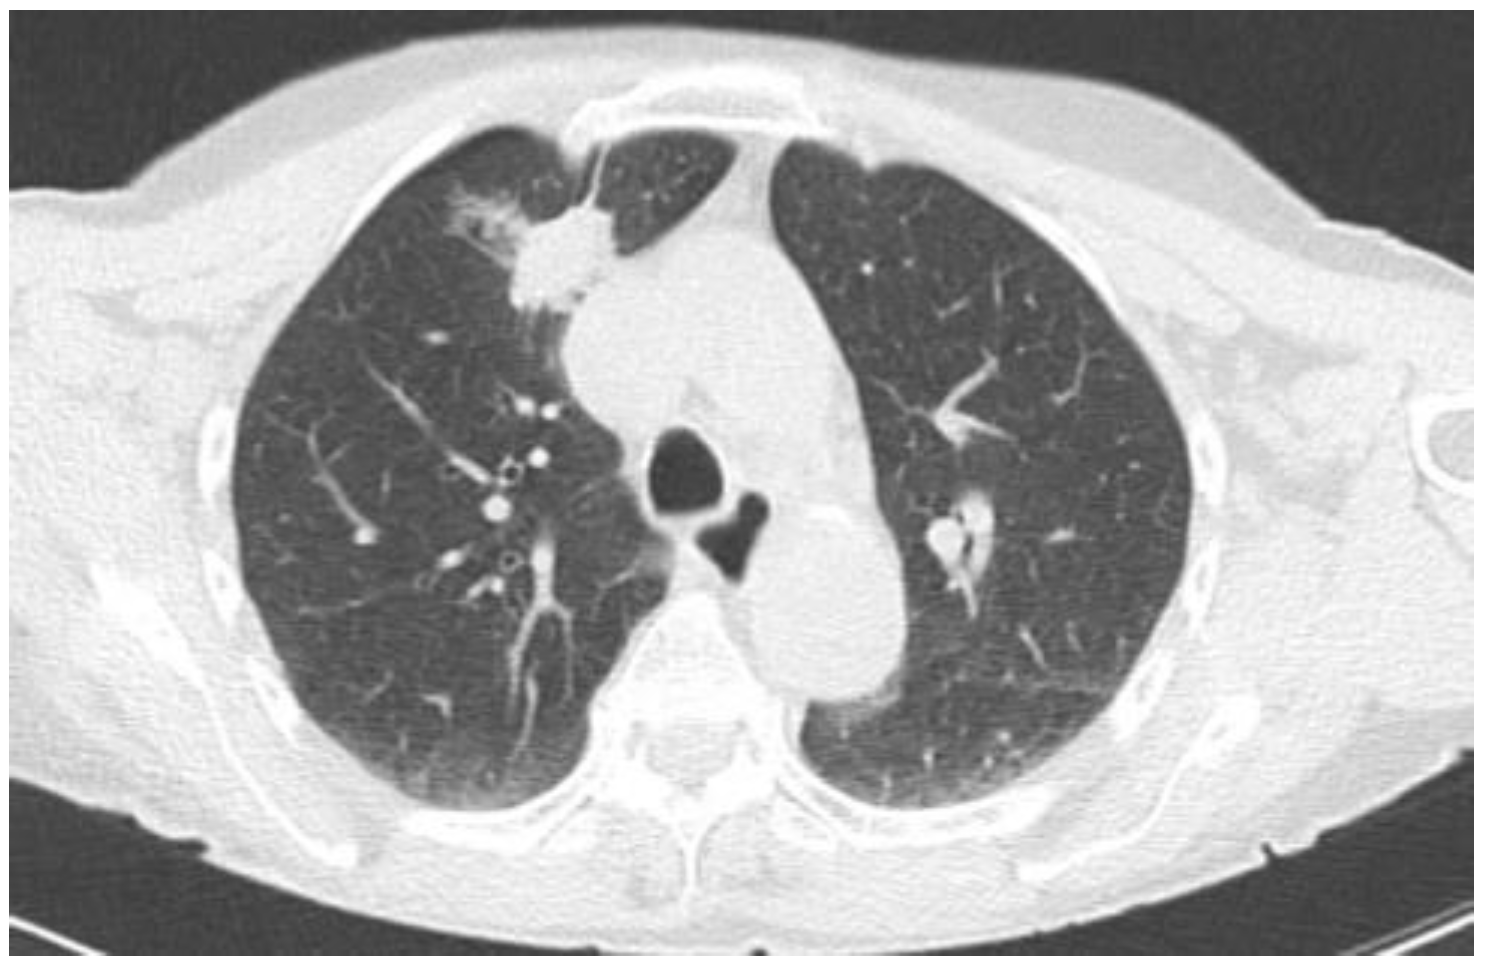

2.2.1. TIME 0: Lesion marking and SPECT Analysis

| Site of lung cancer | LUL | RLL | RUL | LLL | RUL | RUL | LUL | RUL |

| Clinical stage | IB | IB | IB | IA | IA | IB | IB | IB |

| Site of Lung Cancer | Histotype | SPECT-Positive SLN Station | Intraoperative Positive SLN Station | |

|---|---|---|---|---|

| Patient 1 | LUL | ADC | 10 | 10 |

| Patient 2 | RLL | ADC | * | 9 |

| Patient 3 | RUL | ADC | 11 | 11 |

| Patient 4 | LLL | ADC | # | 11 |

| Patient 5 | RUL | ADC | # | 4 |

| Patient 6 | RUL | ADC | 10 | 10 |

| Patient 7 | LUL | SCC | * | 5 |

| Patient 8 | RUL | ADC | 10 | 10 |